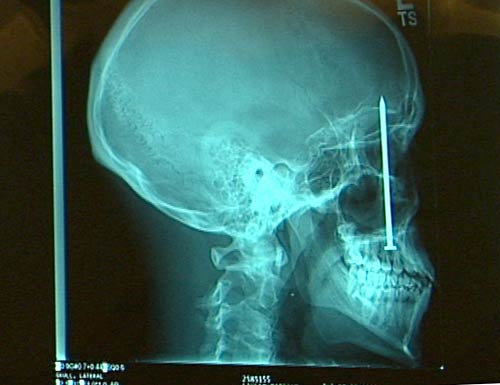

Ci sono voluti sei giorni a Patrick Lawler, un operaio edile di 23 anni del Colorado, per

scoprire la ragione di uno strano mal di denti che lo affliggeva: senza rendersene conto, si era sparato un chiodo in bocca mentre lavorava e l'oggetto metallico è andato a conficcarsi nel cranio, attraverso il palato, senza provocare lesioni vitali. È stato proprio un dentista a scoprire il motivo del lancinante dolore alla bocca del ragazzo. Una macchina sparachiodi a quanto pare aveva funzionato al contrario. Lawler si era reso conto che un chiodo lo aveva sfiorato e si era andato a conficcare nel legno, durante alcuni lavori di costruzione. Quello che il giovane operaio non aveva realizzato è che, nello stesso incidente, un secondo chiodo gli era entrato in bocca, affondando fin quasi al cervello e sfiorandogli l'occhio destro. Il chiodo è stato rimosso dopo un intervento chirurgico durato quattro ore e Lawler si sta ora riprendendo. Le spese mediche per l'operaio, che non ha copertura assicurativa, ammonteranno a 80 mila dollari, ma la famiglia ha raccontato che è di buon umore e i medici hanno sottolineato che ha avuto una enorme fortuna a sopravvivere senza lesioni.

io non me ne intendo, chiedo alla morosa che studia medicina questa sera, ma a vedere le lastre il chiodo è nella cavità oculare, e mi sembra strano che non abbia perso l'occhio, come si vede dalla foto dove tiene il chiodo in mano...secondo me è una bufala......comunque chiedo e poi riferisco da chi se ne intende più di me..

si in effetti dalle lastra risulta chiaro che il bulbo oculare è stato trapassato... eppoi (nel caso fosse vero) non potrebbe farsi risarcire dalla ditta della sparachiodi...

beh dalle mie memorie scolastiche (sono ottico ed ho studiato anatomia oculare) il tipo potrebbe aver avuto un culo paura e il chiodo non ha leso nervi, dalle lastre però sembra che passi in mezzo al nervo ottico, e cmq per due giorni il tizio ogni volta che muoveva l'ochio fregava i muscoli oculari contro il chiodo...

avevo letto su un altro forum, qualche mese fa, una notizia diversa che però riportava le stesse immagini delle radiografie! quella volta "l'inchiodato" era un anziano asiatico che conviveva da anni senza saperlo col chiodo nel cranio ed era stato scoperto per caso durante una visita radiologica di routine.